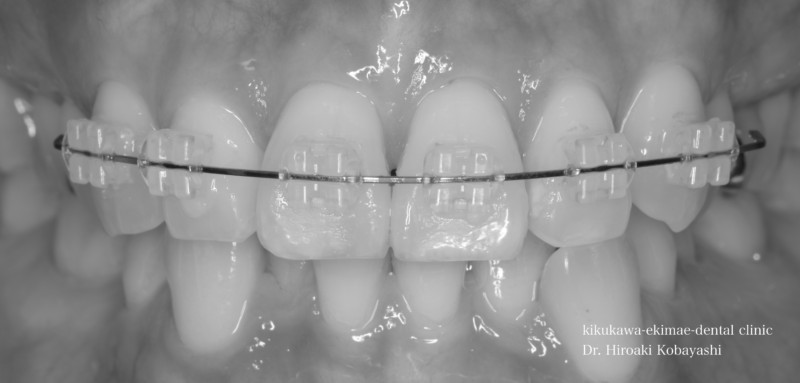

歯並びを気にされて来院されました。見た目改善を目的にワイヤーによる部分矯正を希望されました。 ブラケット装着用のマウスピースを作り、ブラケット装着を行います。   弱い力をかけながら、ワイヤーにより歯を動かします。強い力を急にかけると歯の根が吸収されてしまいます。なので弱い力で歯を動かすことによって根への負担が少なく歯根吸収のリスクが少なくなります。               6ヶ月程度で歯の並びを改善することができました。   before after